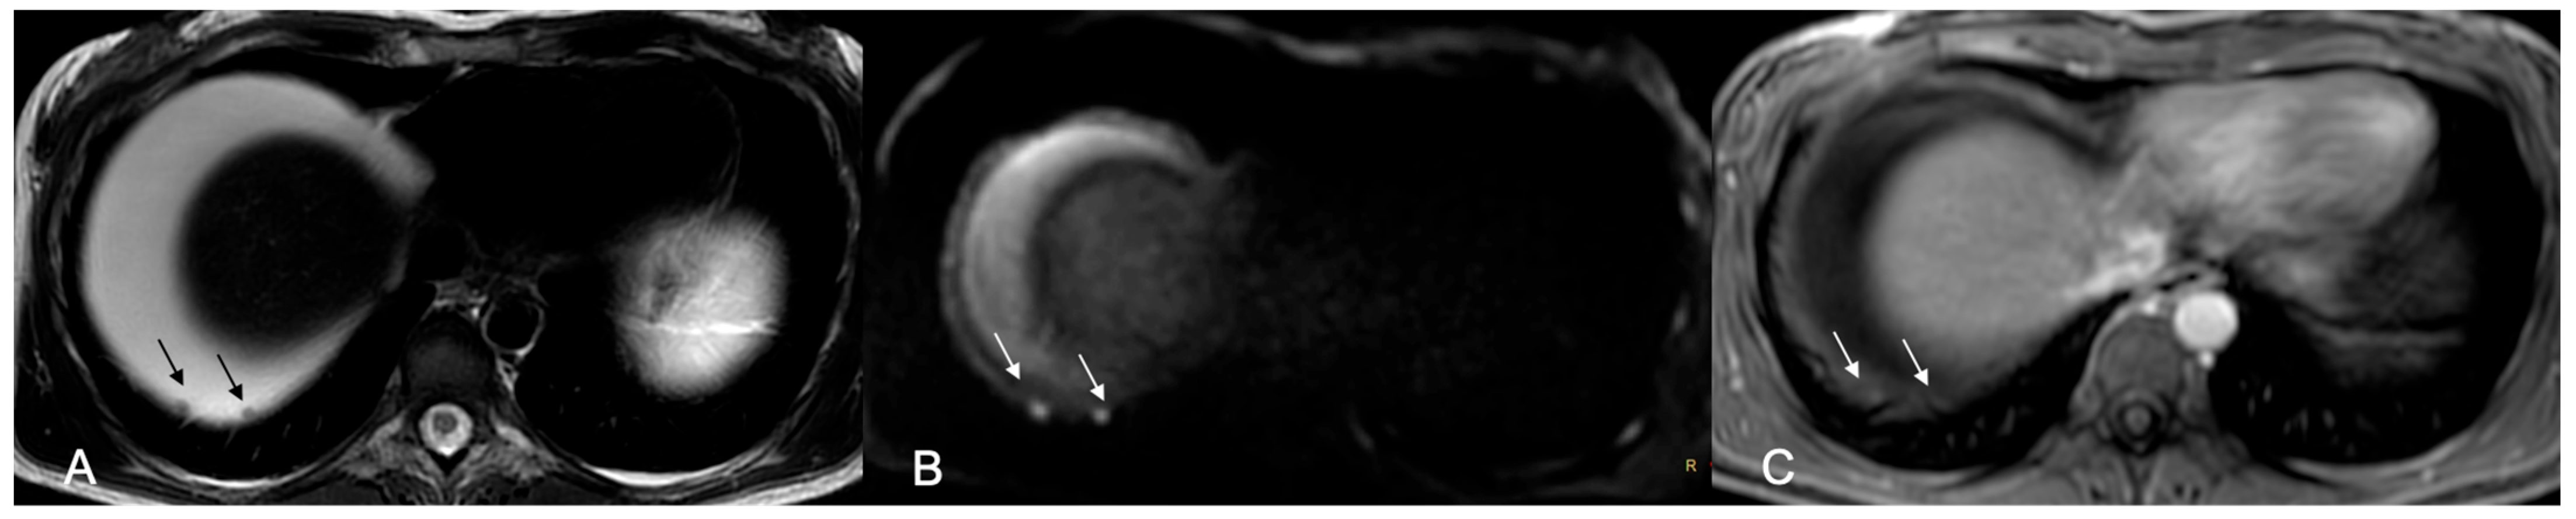

Background/Objectives: Cytoreduction status is a critical prognostic factor in ovarian cancer, yet preoperative selection of patients suitable for primary debulking surgery and accurate prediction of surgical outcome remain challenging. This study aimed to evaluate the prognostic ability of MRI-based Fagotti score and Peritoneal Cancer Index (PCI) for predicting resectability of peritoneal disease in ovarian cancer patients. Methods: This was a prospective single-center observational study. Patients with suspected primary ovarian cancer who underwent preoperative MRI of the abdomen and pelvis with a dedicated protocol were considered. MRI-based Fagotti score and PCI were determined by two readers independently, using a combination of T2W, Diffusion-Weighted Imaging (DWI), and contrast-enhanced T1W sequences. In cases of discordance, a third radiologist reviewed the scans and consensus was reached. ROC analysis and logistic regression were used to evaluate prognostic performance. The reference standard to predict resectability was optimal cytoreduction defined as residual disease ≤1 cm. Results: Forty-six women with epithelial ovarian cancer (mean age 56.3 ± 2.6 years) who underwent preoperative MRI, followed by laparoscopy and/or laparotomy, were included in the study. Both MRI-based Fagotti score and PCI showed high predictive value for predicting resectability (AUC 0.92 and 0.94, respectively). Optimal cut-offs were ≤6 for Fagotti score and ≤20 for PCI. Patients with scores below these thresholds had >60-fold (Fagotti) and >100-fold (PCI) increased odds for successful primary cytoreduction (p < 0.001). Conclusions: MRI-based Fagotti score and PCI may serve as powerful noninvasive predictors of surgical outcome in ovarian cancer. MRI may reliably guide treatment decisions, reducing unnecessary laparotomies and optimizing patient selection.